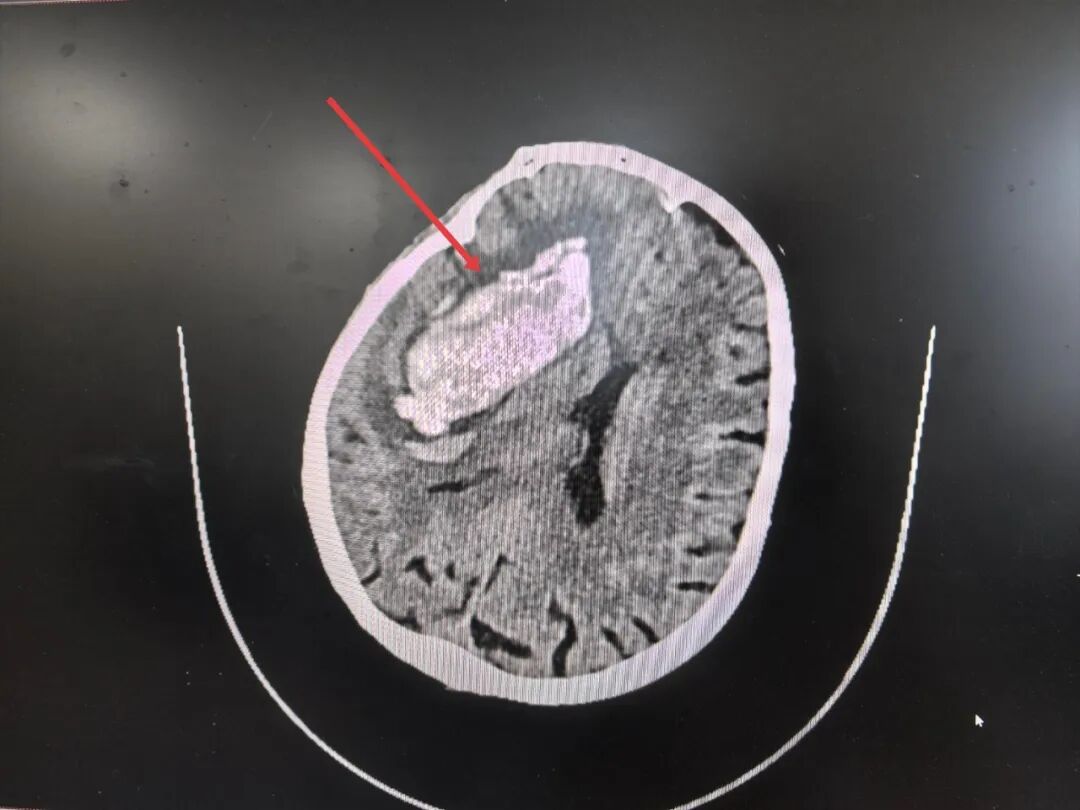

紧急CT扫描结果令人倒吸一口凉气:梁奶奶右侧基底节区(大脑深处要害区域)大量出血,脑疝形成,血块体积巨大,形如“铸型”压迫着脆弱的生命中枢,中线结构被挤压得严重偏移——这是典型的高血压脑出血,且已发展到致命阶段。每一分每一秒的拖延,都意味着脑细胞不可逆转的死亡和生存希望的渺茫。

术前CT:大量血肿压迫

综合外科医生团队迅速集结,仔细研判CT影像后发现患者血肿位置深,紧邻生命中枢脑干。若行传统开颅手术,对这位本就因高血压而脆弱不堪的老人来说风险很大,保守治疗无异于放弃。假如巨大的血肿持续压迫,脑疝随时会夺走她的生命,抢救生命刻不容缓!